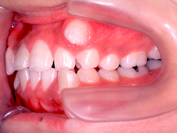

• 歯を抜くかどうかは、矯正治療をする上で非常に重要な問題です。そこで、治療方針を決める際にはまず検査をし、その検査結果を分析します。もちろん患者さんの希望も考慮にいれて、診断の際に最終的な判断をします。

• 歯を抜く場合には、どうして抜かないといけないのか、何本抜くのか、またどの歯を、いつ、どこの歯科医院で抜くのか(当クリニックでは、抜歯はゆきつけの歯科医院へお願いしています)などを分析資料を交えて説明致します。抜歯したスペースは、矯正治療によりどのように利用されますので、隙間が残ることはまずありません。抜く場合にはそれによりかみ合わせや、横顔等がどう変化するのかも、予測画像をお見せすることもできます。